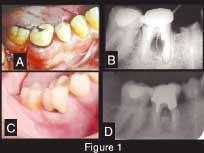

A 42-year-old Caucasian male presented to our clinic for evaluation of a mandibular molar. His previous dentist wanted to extract the tooth, but the patient wanted a second opinion. The patient stated that he would do anything possible to save the tooth. His overall health was good, he did not smoke, he had excellent oral hygiene, and he exhibited no signs of generalized periodontal disease. A year before this initial contact, the patient underwent dental treatment of Tooth No. 30 to repair an ill-fitting post and a crown. He related that some type of surgery was done in the area of the buccal furcation of this tooth to remove part of the post that had apparently perforated the root. After this treatment, he noticed a swelling on the buccal aspect of the furcation that had periods of exacerbation and remission. Despite several attempts to scale and cleanse the area, the problem could not be resolved. The dentist recommended extraction. A radiograph showed a radiolucent lesion in the furcation with a diameter of approximately 0.5 cm (Figure 1). We made another attempt to convince the patient to have the tooth removed and an implant placed, but we were unsuccessful.

Figure 1 — Clinical and radiographic aspect. A: Initial presentation. Observe swelling and redness at the buccal aspect of Tooth No. 30. B: Periapical radiograph showing the radiolucency at the furcation area (pocket depth of 9 mm). C: Clinical presentation four years later. Observe the absence of exudate, the gingival opening at the furcation allowing the patient to clean the pocket, and the porcelain crown in place. D: Periapical radiograph showing the furcation area four years later (pocket depth of 5 mm).